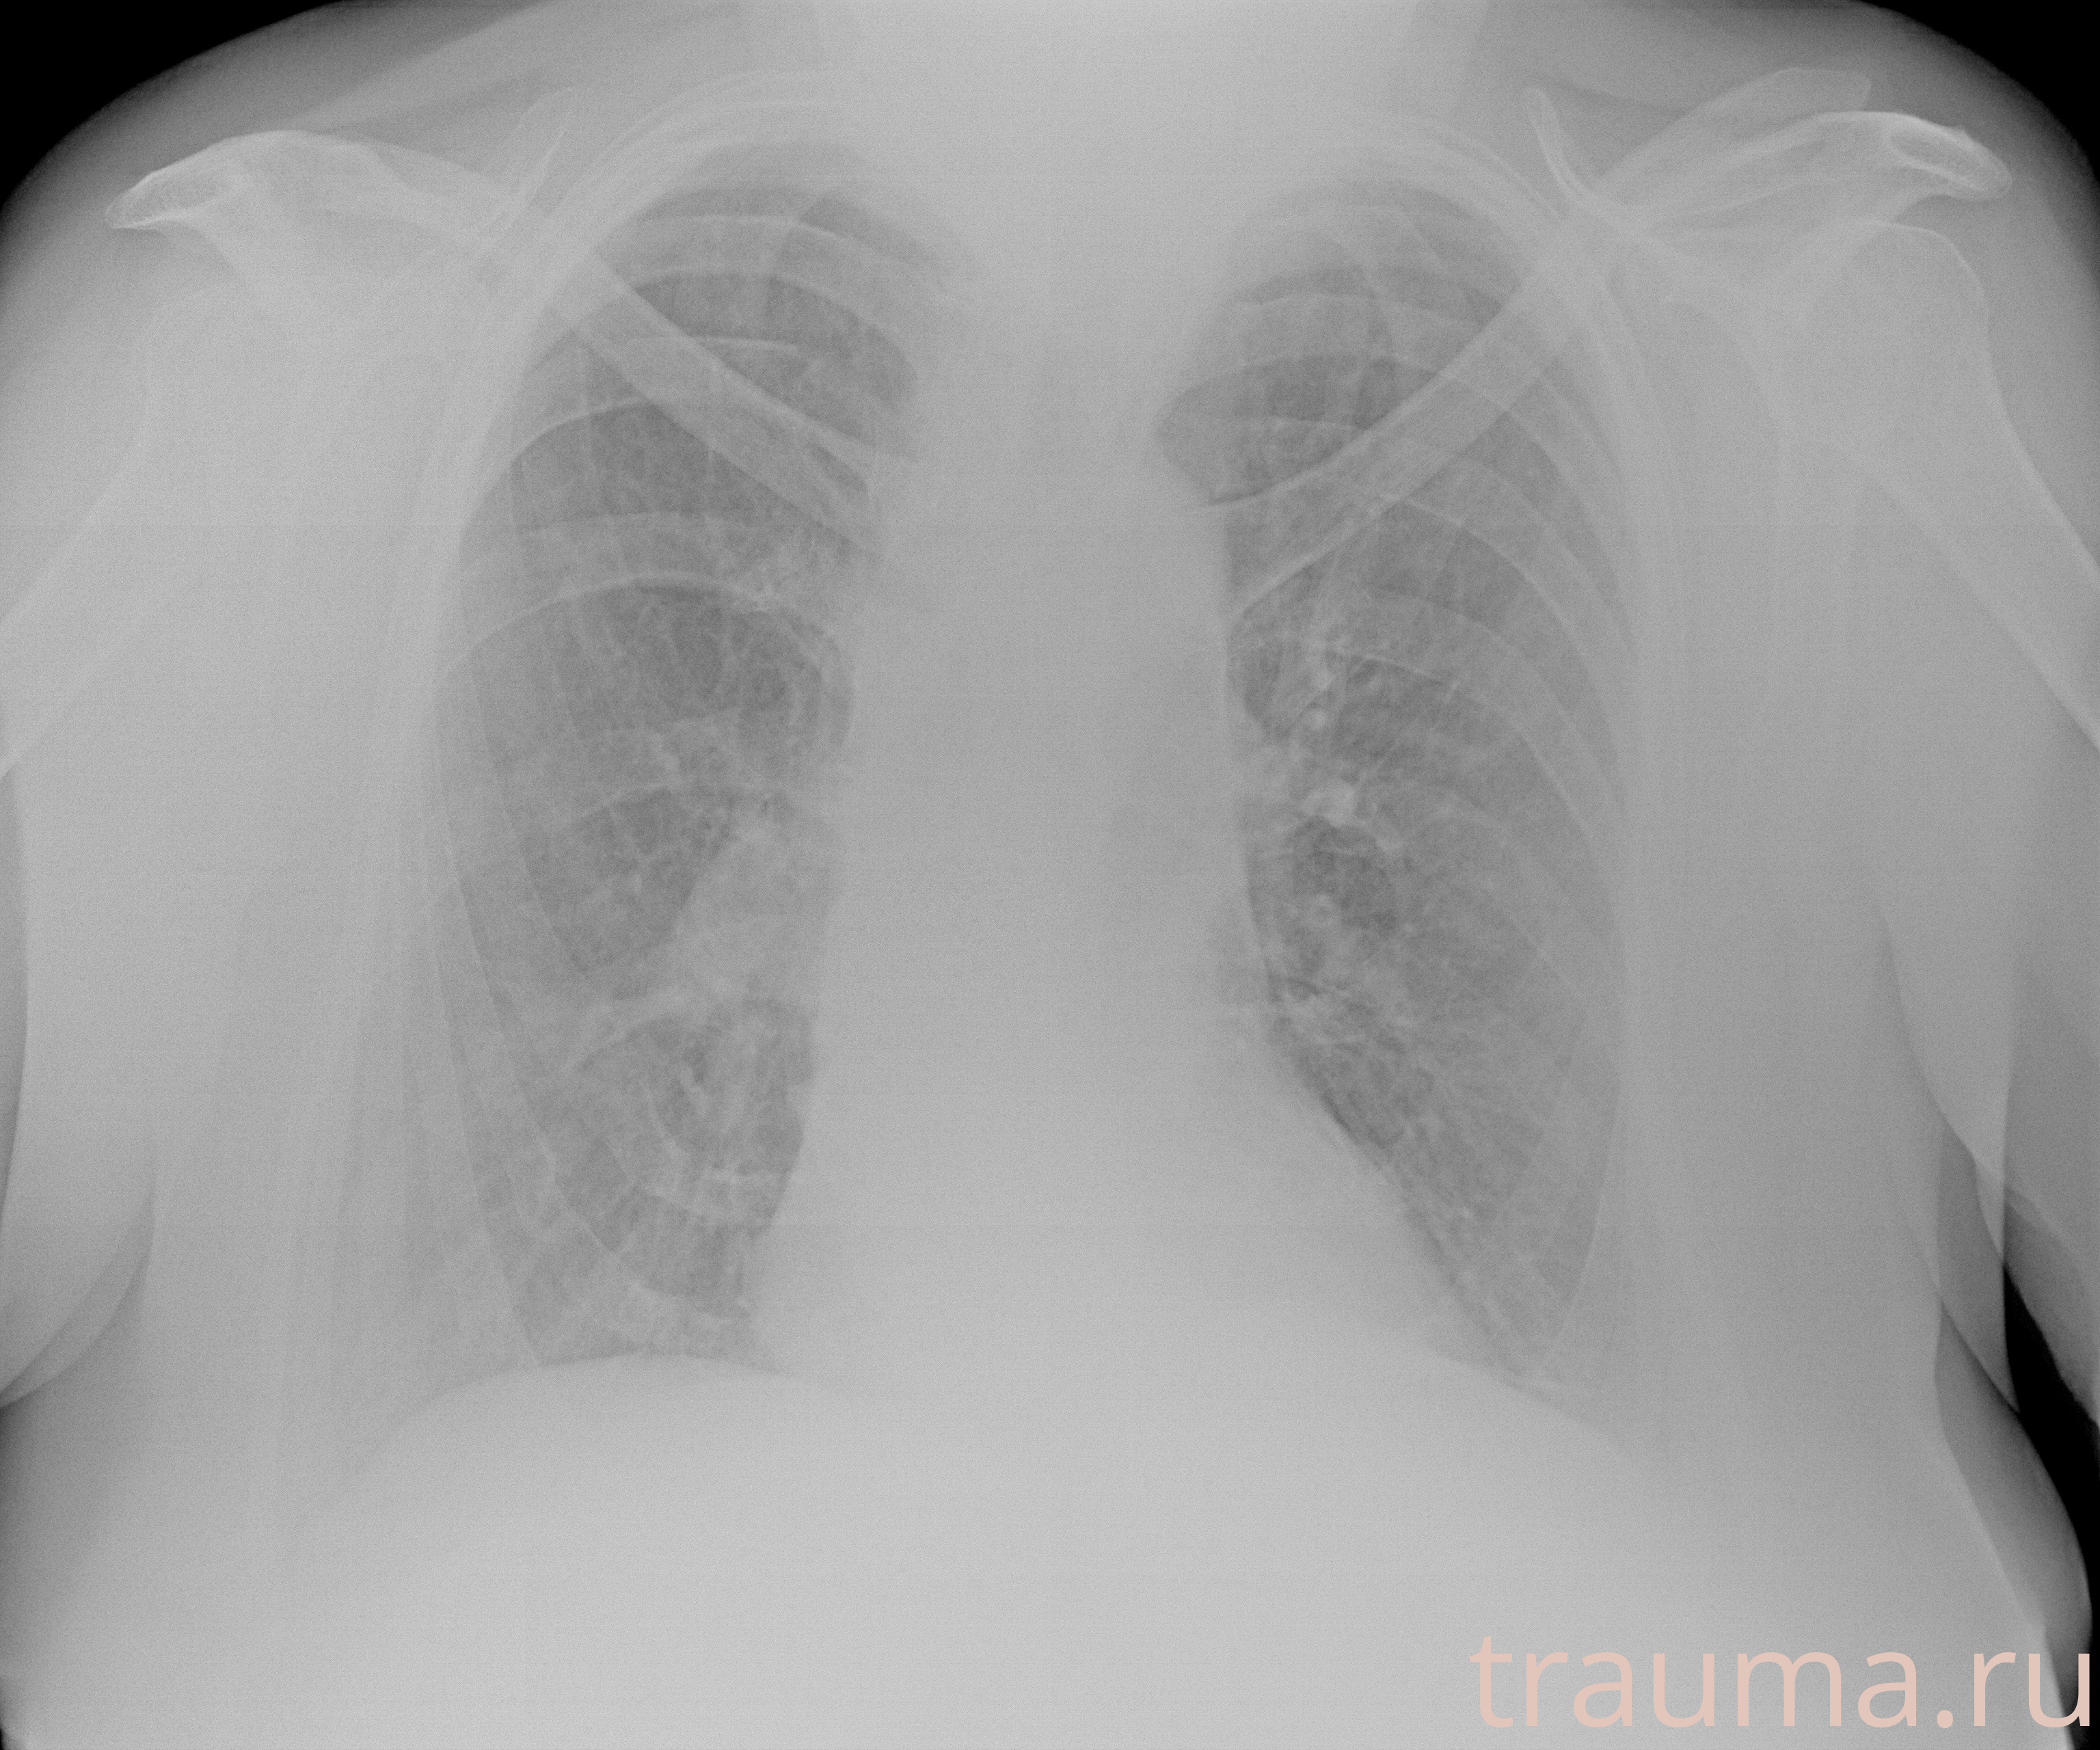

Рентген на дому: по вашему адресу приезжает врач-рентгенолог, травматолог-ортопед с мобильным рентгеновским аппаратом, проводит диагностику травмы или заболевания, делает необходимые рентгенограммы, дает рекомендации по дальнейшему лечению. Получить качественные снимки в домашних условиях возможно благодаря уникальной методике, разработанной МосРентген Центром для института  Склифосовского